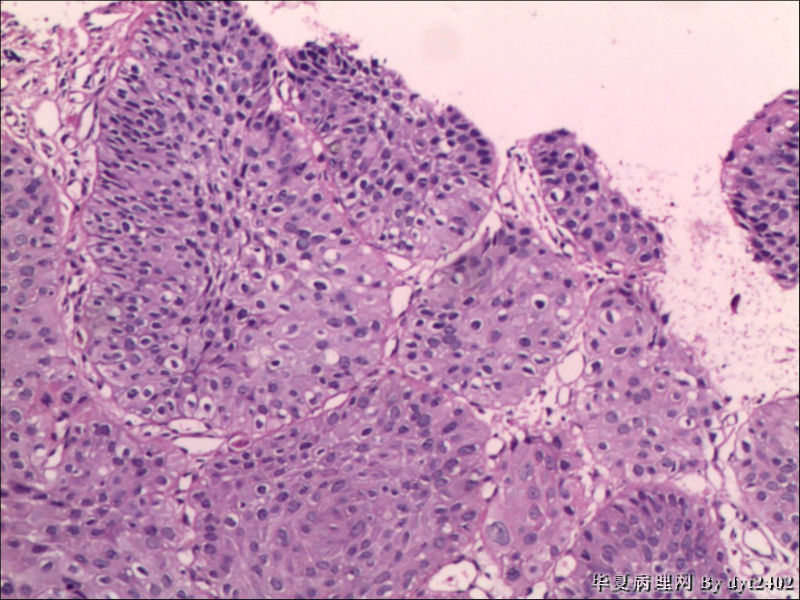

这样的外阴病变 发个原位癌是否合适?

• 这样的外阴病变 发个原位癌是否合适?图4

图4

原位癌够了,不排除其他地方有浸润。

似乎有浸润了

VIN III,做个银染或者标个免疫组化看一下基底膜是否完整。

看上去好像还完整 只是经常看见图5 那样结构的就觉得可能还有更重病变

VIN III